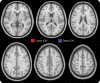

Figure 1. DWI lesions in acute and nonacute time periods

Shown are a parietal DWI lesion seen 1 day after contralateral basal ganglia hemorrhage in a 66-year-old man (A) and a frontal DWI lesion 2 years after contralateral parietal hemorrhage in a 69-year-old man (B). DWI = diffusion-weighted imaging.